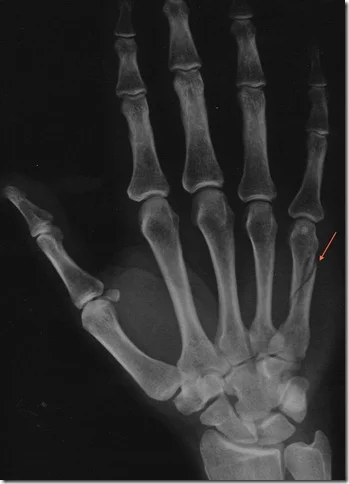

- Radiology:

- AP and Lateral not enough

- Need an special scaphoid view